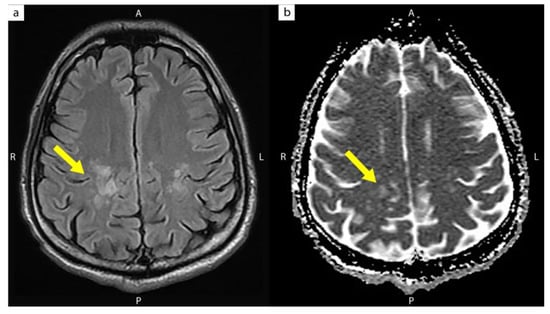

| The present case | 31/M | 4 | 109 | 586,300 | 113 | 3 months | CIDP with progressive quadriparesis (Unmasking IRIS) | High signal intensities over both the posterior corona radiata and centrum semiovale |

| Significantly improved quadriparesis 3 months after anti-MAC and Plasma exchange + IVIG |